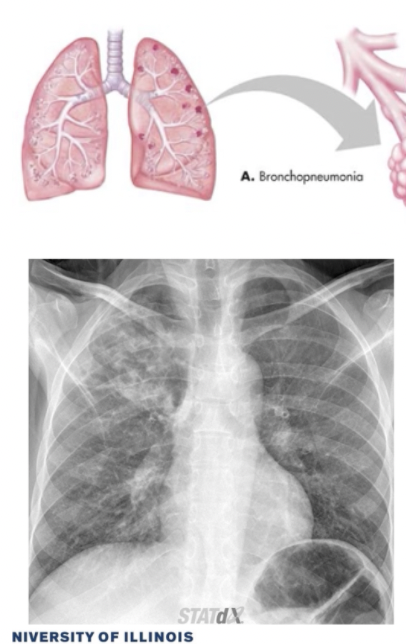

What CXR radiographic findings are typical for segmental/bronchopneumonia

• Multifocal patchy consolidation of secondary lobules with no air bronchogram

What CT findings are typical for segmental/bronchopneumonia

• Can also have ground glass opacity and thickened bronchial opening

What are some usual causes for segmental/bronchopneumonia?

1. lobar pneumonia (generally from bacteria that cause CAP) 2. bronchopneumonia (may be seen if you catch pneumonia early enough and doesn't progress to lobar pneumonia) - image 3. interstitial infiltrates (generally from viruses that cause CAP)